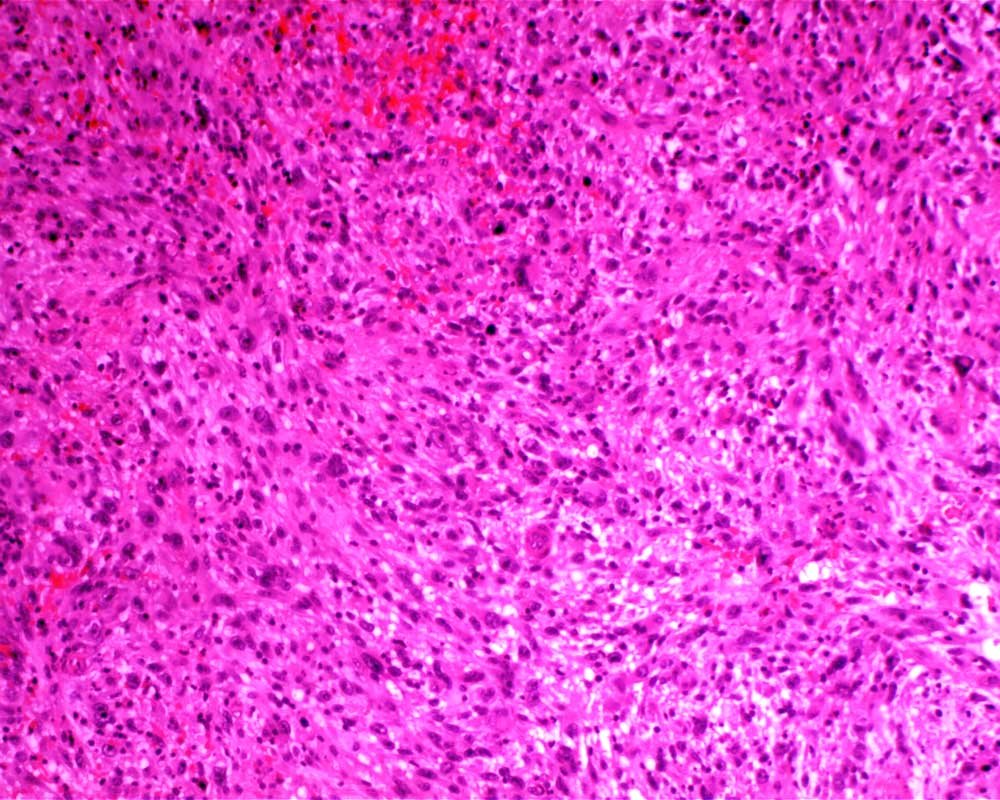

Case: LegMass

Final Diagnosis: